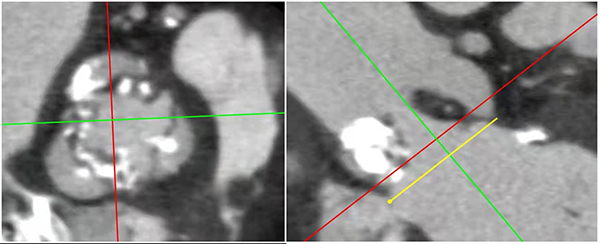

日前,家住柳城的蘭阿公因“反復胸悶、氣促3個月,加重20余天”由外院轉入柳州市人民醫院。當時在外院CT提示雙側胸腔積液、心包積液,兩肺制約性膨脹不全,轉入柳州市人民醫院后仍反復發作胸痛、氣促、頭昏、黑朦,血壓低至75/50mmHg。急診查心臟彩超提示主動脈瓣極重度狹窄,瓣口面積0.5平方厘米,流速5.5m/s,峰值壓差120mmHg;急診CT提示主動脈瓣重度鈣化狹窄,鈣化積分2208,雙側肺水腫。

在柳州市人民醫院結構性心臟病中心郭予潔副院長、吳先球副院長的指導下,心血管內科、麻醉科、重癥醫學科、醫學影像科、心臟外科、血管外科立即開展多學科聯合診療(MDT),最終制定治療方案:由心血管內科陳見紅、苗柳、陶林實施急診經導管主動脈瓣置換術(TAVR)救治患者。

在多學科協作下,急診TAVR手術順利完成,術后患者即刻清醒,拔除氣管插管,患者本人自覺癥狀明顯減輕。術后患者復查心臟彩超提示主動脈瓣狹窄完全解除,心臟縮小,心功能明顯好轉。僅僅經過1周左右的治療,蘭阿公得以逢兇化吉,康復出院!此次蘭阿公的成功救治,得益于柳州市人民醫院結構性心臟病中心團隊對經導管主動脈瓣置換術(TAVR)的熟練運用,以及醫護團隊悉心的照顧,蘭阿公及其家屬紛紛點贊、感謝萬分。